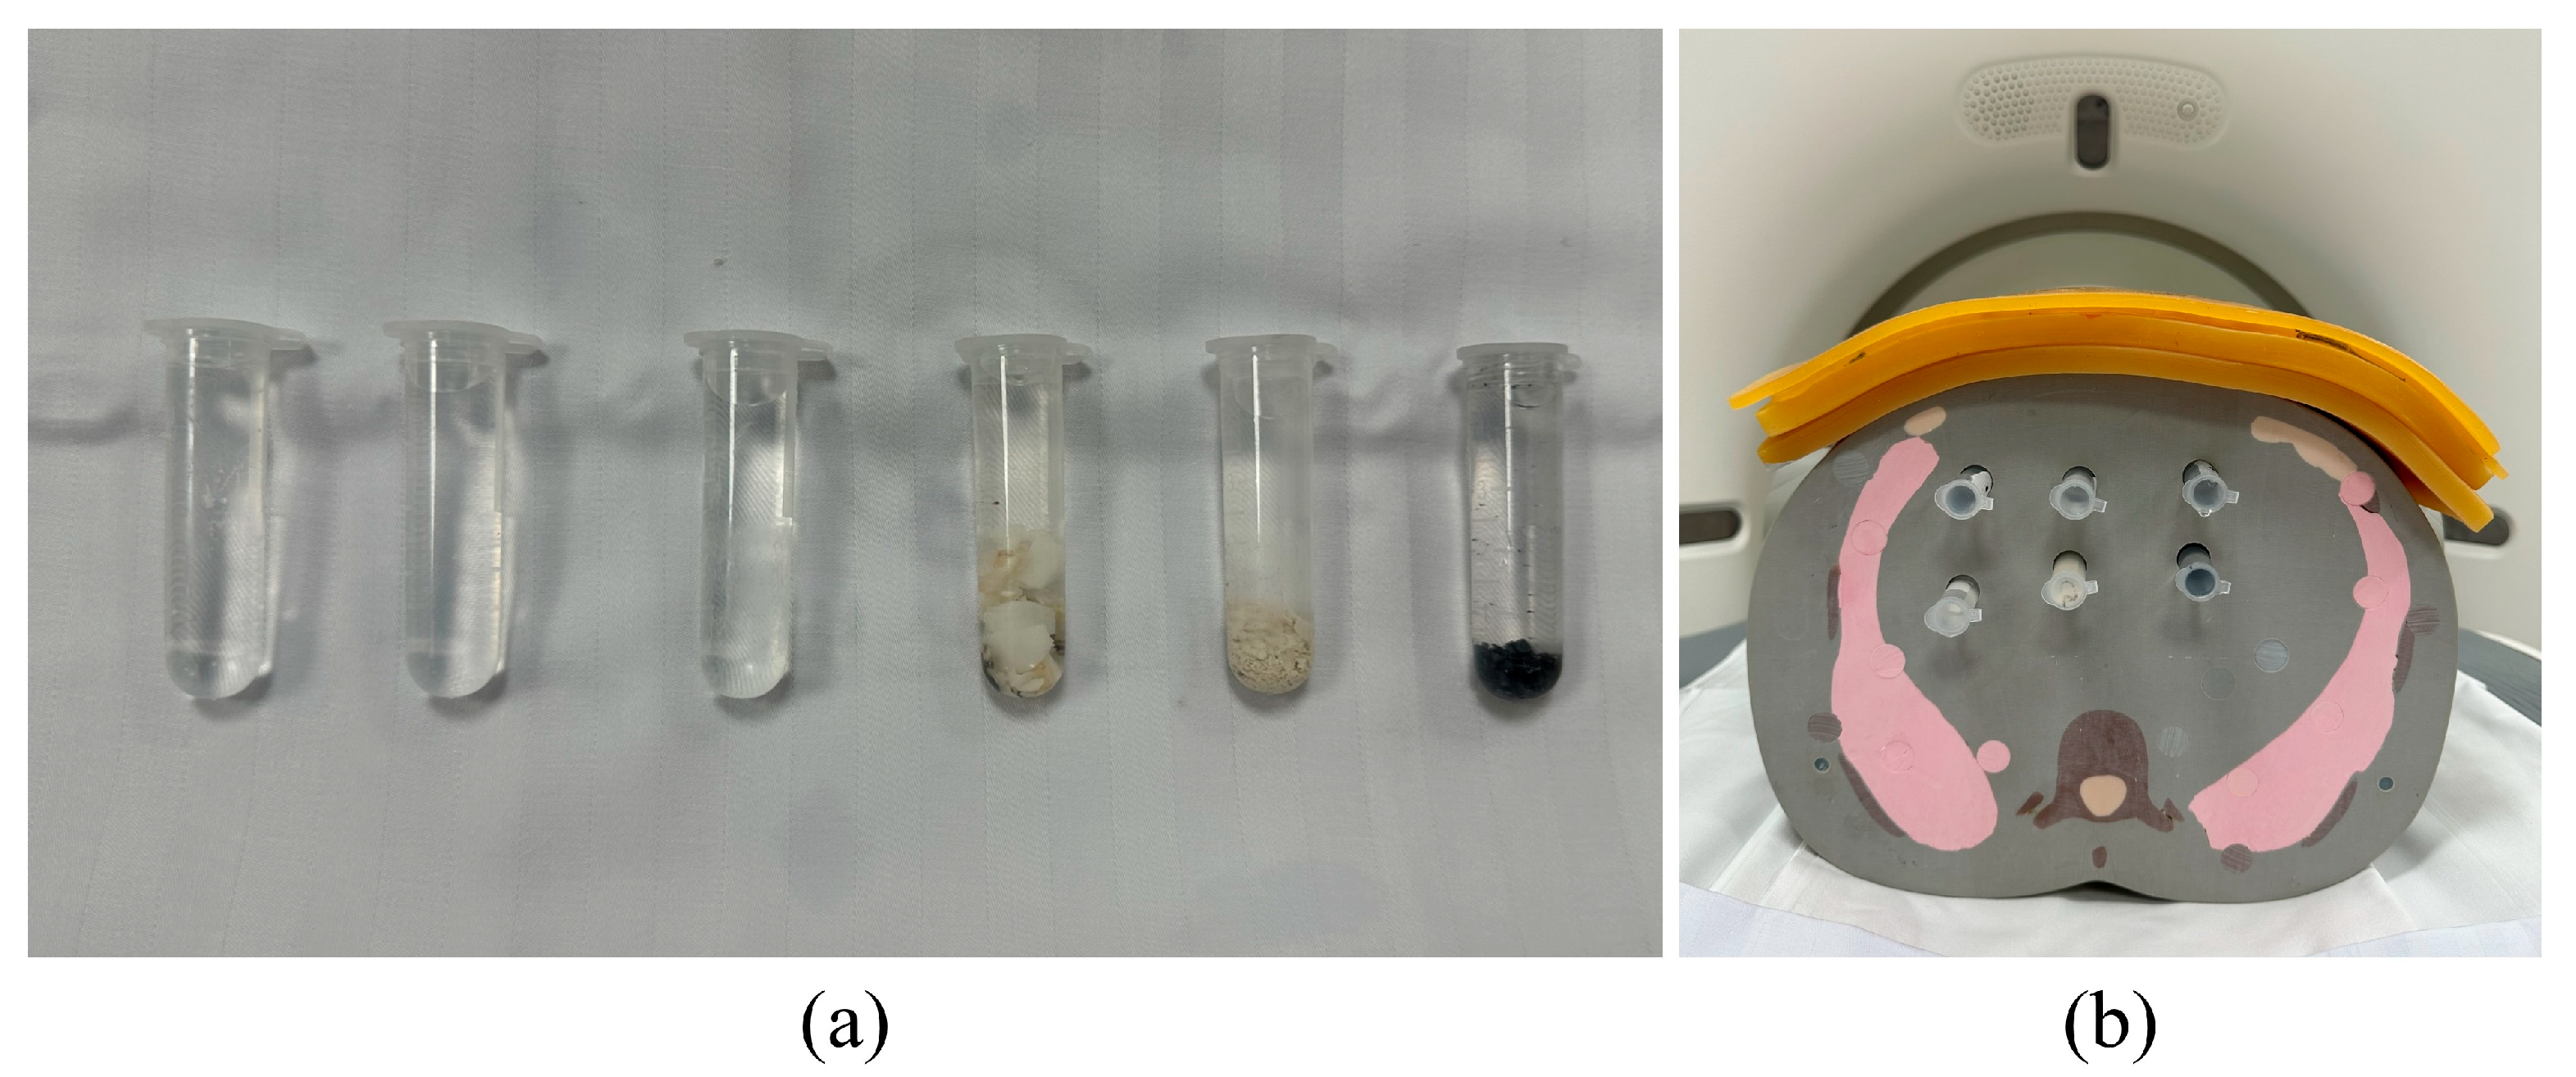

2.4. Phantom Study